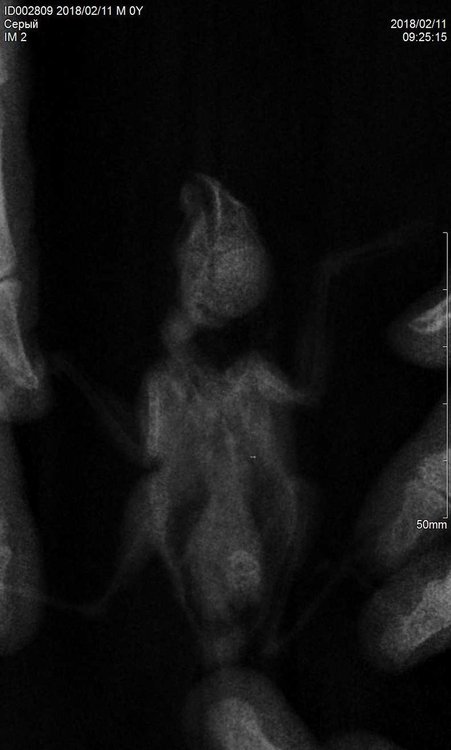

8.1.1. каковы их результаты -  Последний раз сдавали помет на копрограмму  04.02.2018, паразитов не обнаружили, рентген сделали сегодня, 11.02.2018

Рентген птички сделали сегодня, хирург сказал, что в птицах не разбирается, но какое-то затемнение внизу птички есть. Качество не очень, так как птичка очень маленькая и сложно было его сделать. Все снимки прилагаю. Зося, посмотрите, пожалуйста, что с моей птичкой? Чем ей помочь, как лечить? Ей очень плохо! Снегирик боится рук, стрессует, а сейчас вообще в панике. Сидит, дрожит, хвостик поджимает вниз, видимо у него что-то болит.